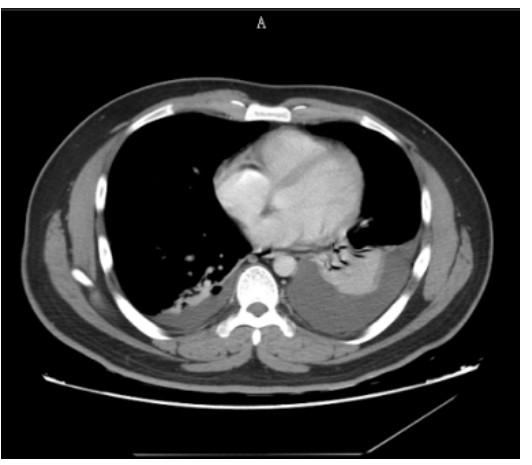

SAP发生呼吸衰竭的原因很复杂,其原因有以下几种。(1)SAP因为炎症反应导致的ARDS(图 1),这是普遍认为的一种原因,但实际上ARDS在SAP患者呼吸衰竭中很多时候是非主要原因。SAP急性期虽然病情进展很快,出现多脏器功能损伤,甚至休克,有类似于脓毒症和感染性休克样的表现,但其炎症反应并不如脓毒症这么强烈,大量的研究可见SAP发生过程其IL-6很少过千,而脓毒症则IL-6动辄大于5 000或10 000,SAP两肺影像学也很少有典型的非心源性肺水肿的双侧阴影,超声下也很少有“B线”表现。但胆道感染引起的脓毒症合并SAP的患者,其ARDS发生率会明显上升。现在随着高脂血症胰腺炎的增加,部分患者到院时同时存在糖代谢障碍,合并有糖尿病酮症,入院前后出现糖尿病酮症昏迷,有些患者会伴有呕吐误吸或者插管时误吸,这类患者在急性期会出现误吸相关的ARDS。(2)SAP是腹腔重症的一种,急性期因为腹膜后急性胰周液体积聚和急性胰周坏死物积聚,导致腹腔压力进行性升高,随之出现横膈抬高,两肺压缩,从而导致“小肺”,这和ARDS的“baby lung(小肺)”不同(图 1: ARDS;图 2、3: 腹内压14 mmHg和23 mmHg的对比,明显看到图 3呈现横膈抬高引起的小肺)。因横膈位置上抬导致小肺是SAP呼吸衰竭的主要原因。(3)两下肺不张(图 4)和胸腔积液(图 5):这两个原因也是导致SAP呼吸衰竭的主要原因,因为膈下刺激,导致两下肺的不张和大量胸腔积液常见于SAP患者,这两种原因导致的呼吸衰竭也和ARDS不同。(4)其他原因:胸腔出血、肺梗死和气胸亦可见于SAP相关呼吸衰竭,但相对少见。

| 图 5 胸腔积液 |